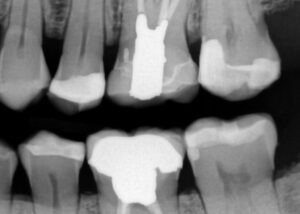

March 10, 2026 (Afternoon tea pics 2341.3: Kerr Simplishade | Rhondium DME | Garrison Dental Solutions – North America) Getting d o w n with DME. #RhondiumDME #KerrSimplishade #GarrisonCompositight Previous Post